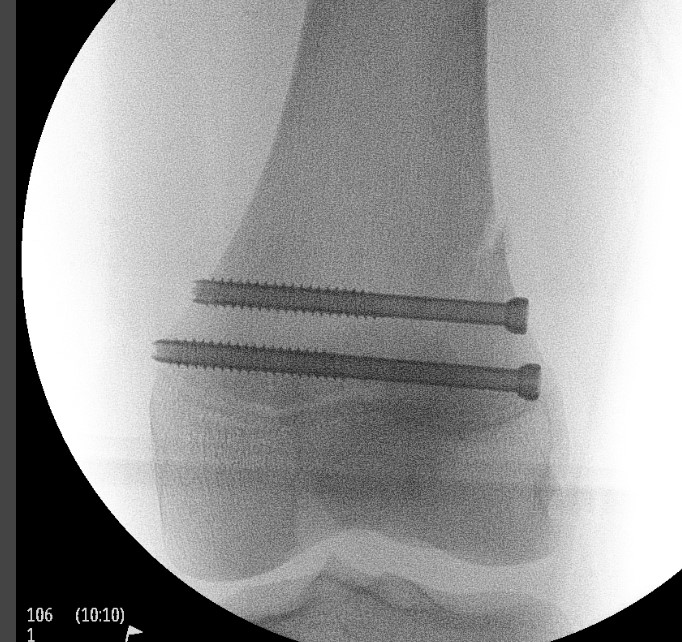

Options

1. Physeal sparing metaphyseal screw in SHII

- good option if Thurston-Holland fragment large enough

2. Smooth transphyseal large K wires / Steinman pin

- SHI

- SHII with small Thurston-Holland fragment